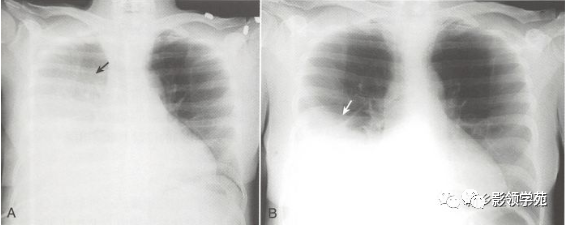

半月征

因为肺的自然弹性回缩,在正位投射上胸腔积液的外侧边较内侧边高。这形成了胸腔积液典型的半月形。

侧位投射上,积液积聚呈U形改变,前方和后方上升的高度一致。

识别出半月形的异常肺密度增强提示胸腔积液。